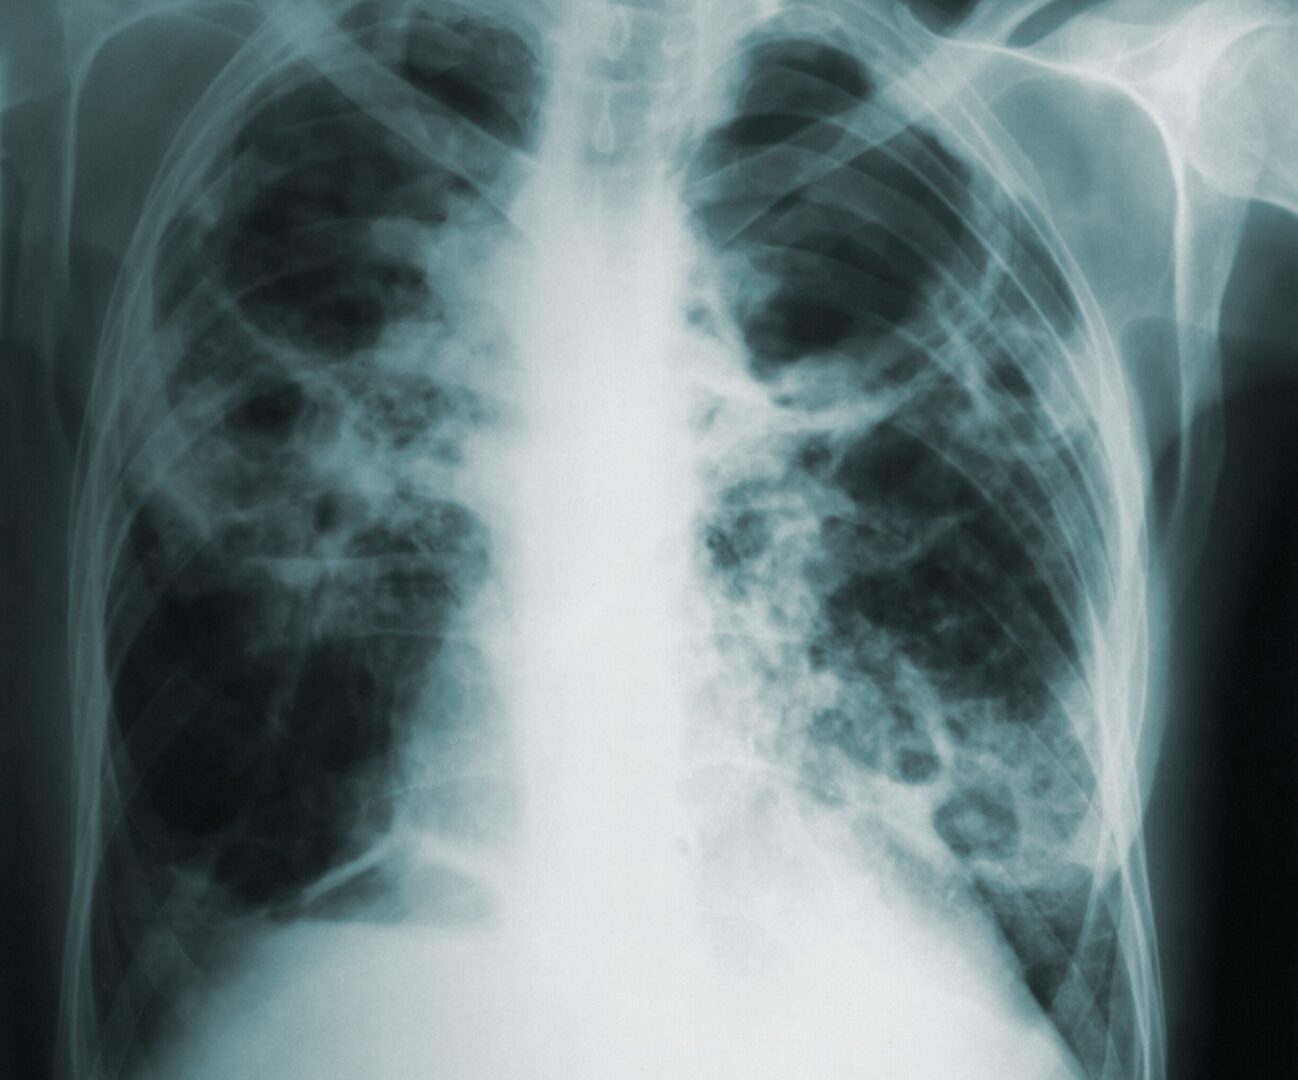

The number of influenza, COVID-19 and RSV cases continues to climb in San Diego County, but local hospitals Monday clarified that they are not seeing a massive spike in hospitalizations or being forced to use overflow tents as triage.

While the local health systems are managing patients, the percentage of those visiting emergency departments with signs of respiratory illness has increased 2% over the previous week, from 7% to 9%. There were a total of 1,732 flu cases reported last week compared to 1,201 the previous week.

The total lab-confirmed cases to date increased to 5,471, compared to 291 at the same time last season and a 259 prior 5-year average during the same week. There have been two influenza deaths this season.

A total of 2,016 COVID-19 cases were reported to the county in the past seven days increasing the region’s total to 933,270. The 2,016 cases reported in the past week were higher compared to the 1,702 infections identified the previous week. An additional 12 deaths were reported in the past week, increasing the cumulative total to 5,543.